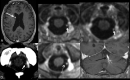

Imaging Findings of Benign Enhancing Foramen Magnum Lesions